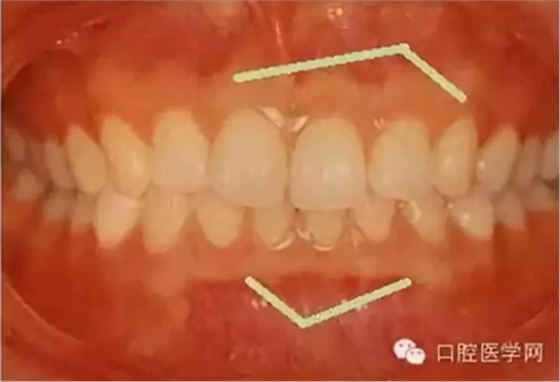

在臨床上我們需要把牙槽骨增生和骨隆突區(qū)分開來,骨隆突是在頜骨上的生理性骨性突起,并不是一個(gè)疾病癥狀,也不是疾病的表現(xiàn),比如舌側(cè)骨隆突、上頜骨骨隆突、下頜隆突是在第三磨牙和雙尖牙舌側(cè)的一個(gè)生理性突起。

2、對(duì)于生理性的骨隆突,一般也不進(jìn)行治療,在第三磨牙和雙尖牙舌側(cè)牙槽骨的舌側(cè)骨隆突、上頜骨骨隆突、下頜隆突等生理性突起,在進(jìn)行活動(dòng)義齒修復(fù)的時(shí)候應(yīng)該避讓開這些地方,以免義齒佩戴后產(chǎn)生壓痛。